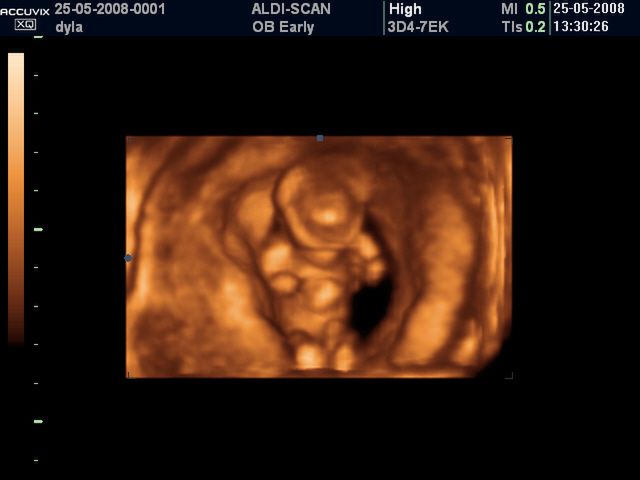

/ 3Płód w 11 tygodniu ciąży - bicie serca

W 11 tygodniu można usłyszeć bicie serca dziecka